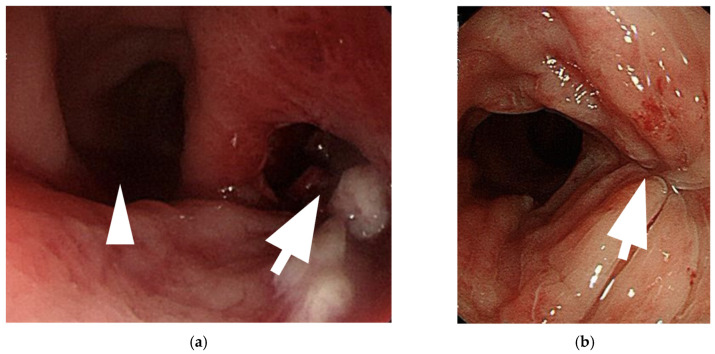

背景与目的:性别肯定手术可显著改善跨性别女性的生活质量和心理健康。在各种技术中,乙状结肠阴道成形术因其能够提供足够的阴道深度和内在润滑而被广泛应用。然而,它也有风险,新阴道穿孔是一种严重但未被报道的并发症。材料与方法:本文综述了新发阴道穿孔的病因、临床表现、诊断和治疗。我们进行文献回顾,分析报告的病例和治疗策略。此外,我们提出了一个来自我们机构的病例,以突出诊断和治疗方面的挑战。结果:新阴道穿孔是由机械损伤、缺血、感染或乙状结肠段结构缺陷引起的。常见的危险因素包括不适当的扩张、内径狭窄和血管损伤。症状从轻微的盆腔不适到腹膜炎和败血症。计算机断层扫描(CT)是诊断的金标准。轻微病例保守治疗有效,严重病例需手术修复。结论:新的阴道穿孔是罕见的,但可能危及生命。未来的研究应改进手术技术、扩张方案和组织工程解决方案。标准化指南和患者教育对于预防和改善结果至关重要。

Background and Objectives: Gender affirmation surgery significantly improves the quality of life and psychological well-being of transgender women. Among various techniques, sigmoid vaginoplasty is widely performed due to its ability to provide adequate vaginal depth and intrinsic lubrication. However, it carries risks, with neovaginal perforation being a serious yet underreported complication. Materials and Methods: This review examines the etiology, clinical manifestations, diagnosis, and management of neovaginal perforation. A literature review was conducted to analyze reported cases and treatment strategies. Additionally, we present a case from our institution to highlight diagnostic and therapeutic challenges. Results: Neovaginal perforation arises from mechanical trauma, ischemia, infection, or structural weaknesses in the sigmoid segment. Common risk factors include improper dilation, introital stenosis, and vascular compromise. Symptoms range from mild pelvic discomfort to peritonitis and sepsis. Computed tomography (CT) is the gold standard for diagnosis. Conservative management is effective in mild cases, whereas severe cases require surgical repair. Conclusions: Neovaginal perforation is rare but potentially life-threatening. Future research should refine surgical techniques, dilation protocols, and tissue engineering solutions. Standardized guidelines and patient education are essential for prevention and improved outcomes.